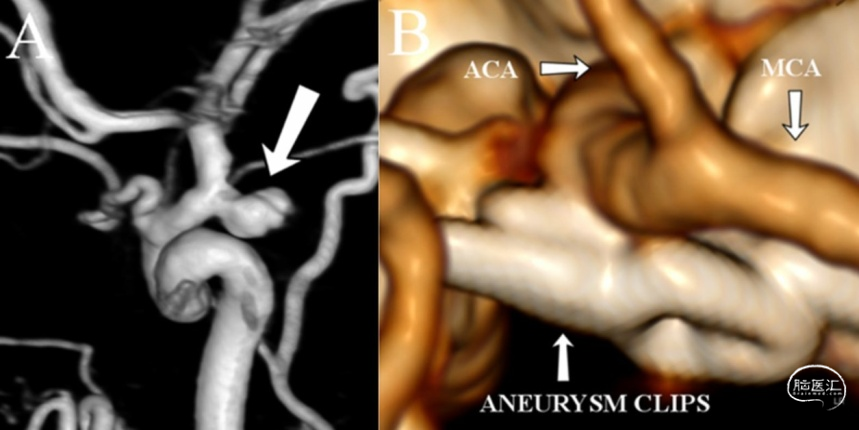

动脉瘤性蛛网膜下腔出血(aSAH)患者约有25%死于院前或急诊室。SAH引起的猝死第一症状是意识丧失(loss of consciousness,LOC),这也是非致命性SAH的常见症状。对动脉瘤破裂时LOC的病理生理机制仍有争议。芬兰赫尔辛基大学神经外科的Ilari Rautalin等在2021年2月的《Neurocrit Care》杂志报道1例aSAH患者在没有心脏停止搏动的情况下,出现短暂的颅内循环停止而意识丧失;这种颅内循环停止是短暂的,伴临床状态不佳,但可以恢复较好。1例有吸烟史、高血压和哮喘的50-60岁患者在运动时意识丧失,接受复苏后患者在几分钟内意识恢复。入院时患者神志清醒,无神经功能缺失,但血压偏高和头痛严重。进行CT检查时,患者再次意识丧失,并出现窦性心动过缓,但瞳孔大小及光反射正常。即刻气管插管,行头部CT扫描和CTA检查。在CTA检查期间,收缩压突然升高超过200mmHg。给予镇静和抗高血压药物治疗,双侧瞳孔变大、光反射消失。CTA成像显示,大脑中动脉近端和大脑前动脉水平远端的颅内循环停止,但颅外动脉正常充盈(图1a)。CT扫描示弥漫性SAH合并脑内血肿,未发现颅内动脉瘤。快速输注甘露醇后,患者瞳孔在10分钟内恢复正常。在第一次CTA的57分钟后患者状态稳定,再次CTA检查显示颅内循环恢复(图1b),并有再出血迹象,右后交通动脉处有可疑病灶。接着,DSA检查发现,右侧后交通动脉瘤(图2a)。住院期间的心电图和生物标志物均未提示发生过应激性心肌病。给予显微手术夹闭动脉瘤(图2b),并清除脑内和硬膜下血肿。患者出现脑积水,采用脑室腹腔分流术。一年后,患者重返工作岗位,并进一步进行神经认知后遗症的康复治疗。

图2. A.DSA显示右后交通动脉瘤。B.术后CTA示动脉瘤夹闭。通过分析该患者发生LOC但不伴有心脏骤停时进行的CT和CTA检查结果,作者认为aSAH患者发生LOC,很可能是短暂的颅内循环停止所引起。建议进一步的临床试验证实此现象并非为偶然发生。